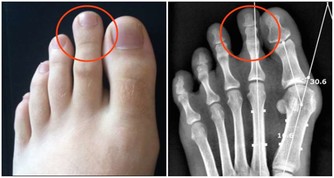

即使三個條件都滿足,少量艾滋病毒進入身體,病毒量也通常達不到染病的程度。而且,人體自身的免疫功能,面對艾滋病毒也會啟動防護機制。

因此,口腔潰瘍出血在概率上的確存在感染的可能,但被感染的機率微乎其微。

至於很多人擔心,有口腔潰瘍的情況下接吻感染,就​​算真的發生,也是因為血液暴露,歸於血液傳播,而不能說接吻是艾滋病的一個傳播途徑。